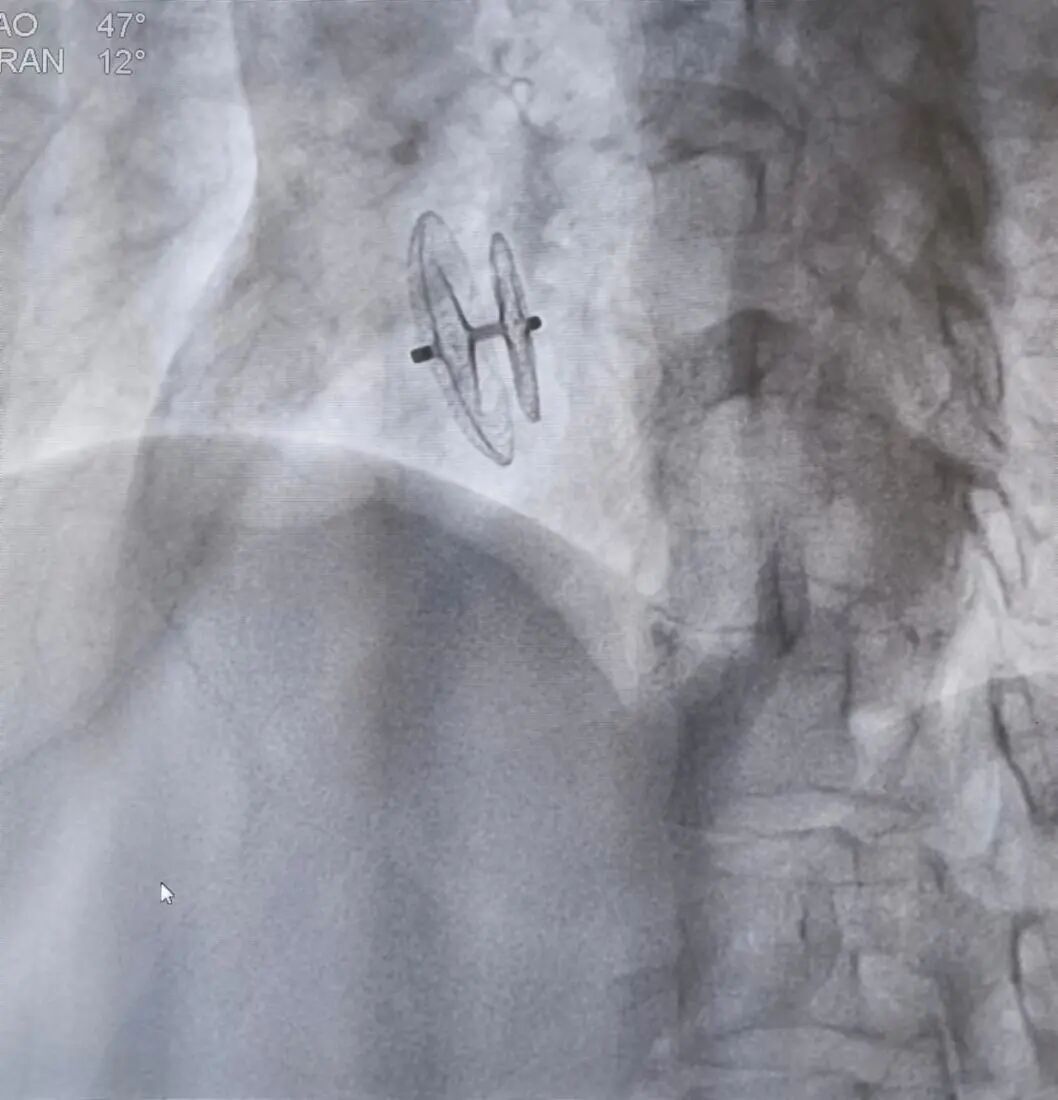

头痛竟然是因为心脏有个“漏洞”。近日,我院心内科执行主任毛庆团队揭开了一名患者头痛多年的秘密,为患者实施手术后,顺利解除了困扰患者多年的病痛。 患者李某(化名),47岁女性,常年发作性头痛,且多在紧张、疲劳、失眠后出现,头颅CT未见明显异常,李某深受其苦。 毛庆团队怀疑患者头痛可能是心脏卵圆孔未闭(PFO)造成的,行心超+右心声学造影后发现患者果然卵圆孔未闭且合并房间隔膨出瘤形成,结构较为复杂。证实推断后,毛庆团队为患者实施手术。 手术当日,毛庆和南京市第一医院心内科周陵主任精诚合作,与心内科主任医师章传龙默契配合,在超声科周黎明主任术中全程超声辅助下,顺利、高效完成PFO封堵术。术中及术后超声均表明封堵器在位良好,未见残余分流。术后患者恢复良好,头痛较前明显减轻。困扰多年的病症一夕根除,患者的脸上终于露出了笑容。 “卵圆孔未闭是成人中最为常见的先天性心脏异常。卵圆孔未闭与减压病、偏头痛等的发病有关。”毛庆说。 卵圆孔是心脏房间隔中部的一个开放区,位于胚胎期原发间隔与继发间隔的交界处。卵圆孔一般在婴儿出生后2个月左右闭合,超过一年左未融合则形成卵圆孔未闭。成人中约有25%左右的卵圆孔不能完全闭合。患有PFO的患者,容易导致偏头痛,短暂性脑缺血发作、不明原因的头晕、晕厥,甚至导致脑卒中。经皮介入PFO封堵术是目前治疗PFO的优选方法,具有安全、有效、创伤小的优点。 心内科提醒广大患者,如常年有不明原因的头痛、头晕、晕厥发作,一定要到正规医院筛查卵圆孔未闭。我院心内科团队将一如既往为溧水人民的心脏健康保驾护航。 |